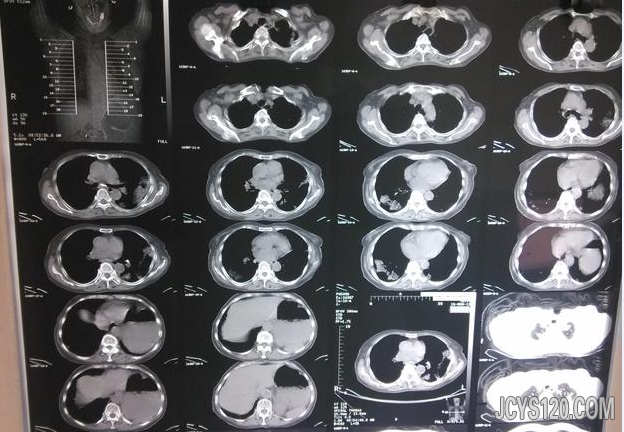

• 双肺病变的一个病号 attach_img agree

• 玻璃箱 2013-4-16

• 患者女,76岁,此次以咳嗽、发热半月余为主诉。半月余前患者无明显诱因出现咳嗽、发热,体温最高达38.5℃,无明显咳痰,无胸痛、咯血、呼吸困难,无头痛、头晕,无恶心、呕吐,无腹痛、腹泻,无尿频、尿急等,就诊于 ...  阅读全文>